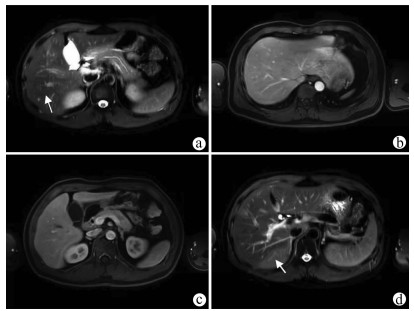

IgG4-related autoimmune hepatitis with subacute liver failure as the initial manifestation: A case report

Li JIANG, Huimin LIU, Qing MAO

2022, 38(1): 170-173. DOI: 10.3969/j.issn.1001-5256.2022.01.028

Abstract(1589) HTML (432) PDF (3941KB)(87)

Abstract: